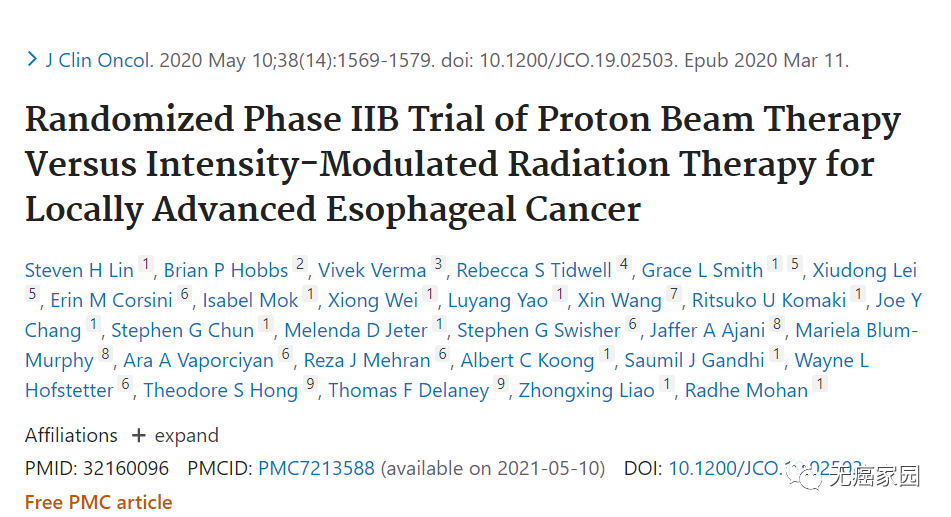

长期以来,人们都知道传统放疗使用的X射线(也称为光子)疗法会导致各种副作用,比如食管癌的放疗会造成不同程度的吞咽不适,脑瘤的放疗会导致精神不振等症状,但实际上接受...